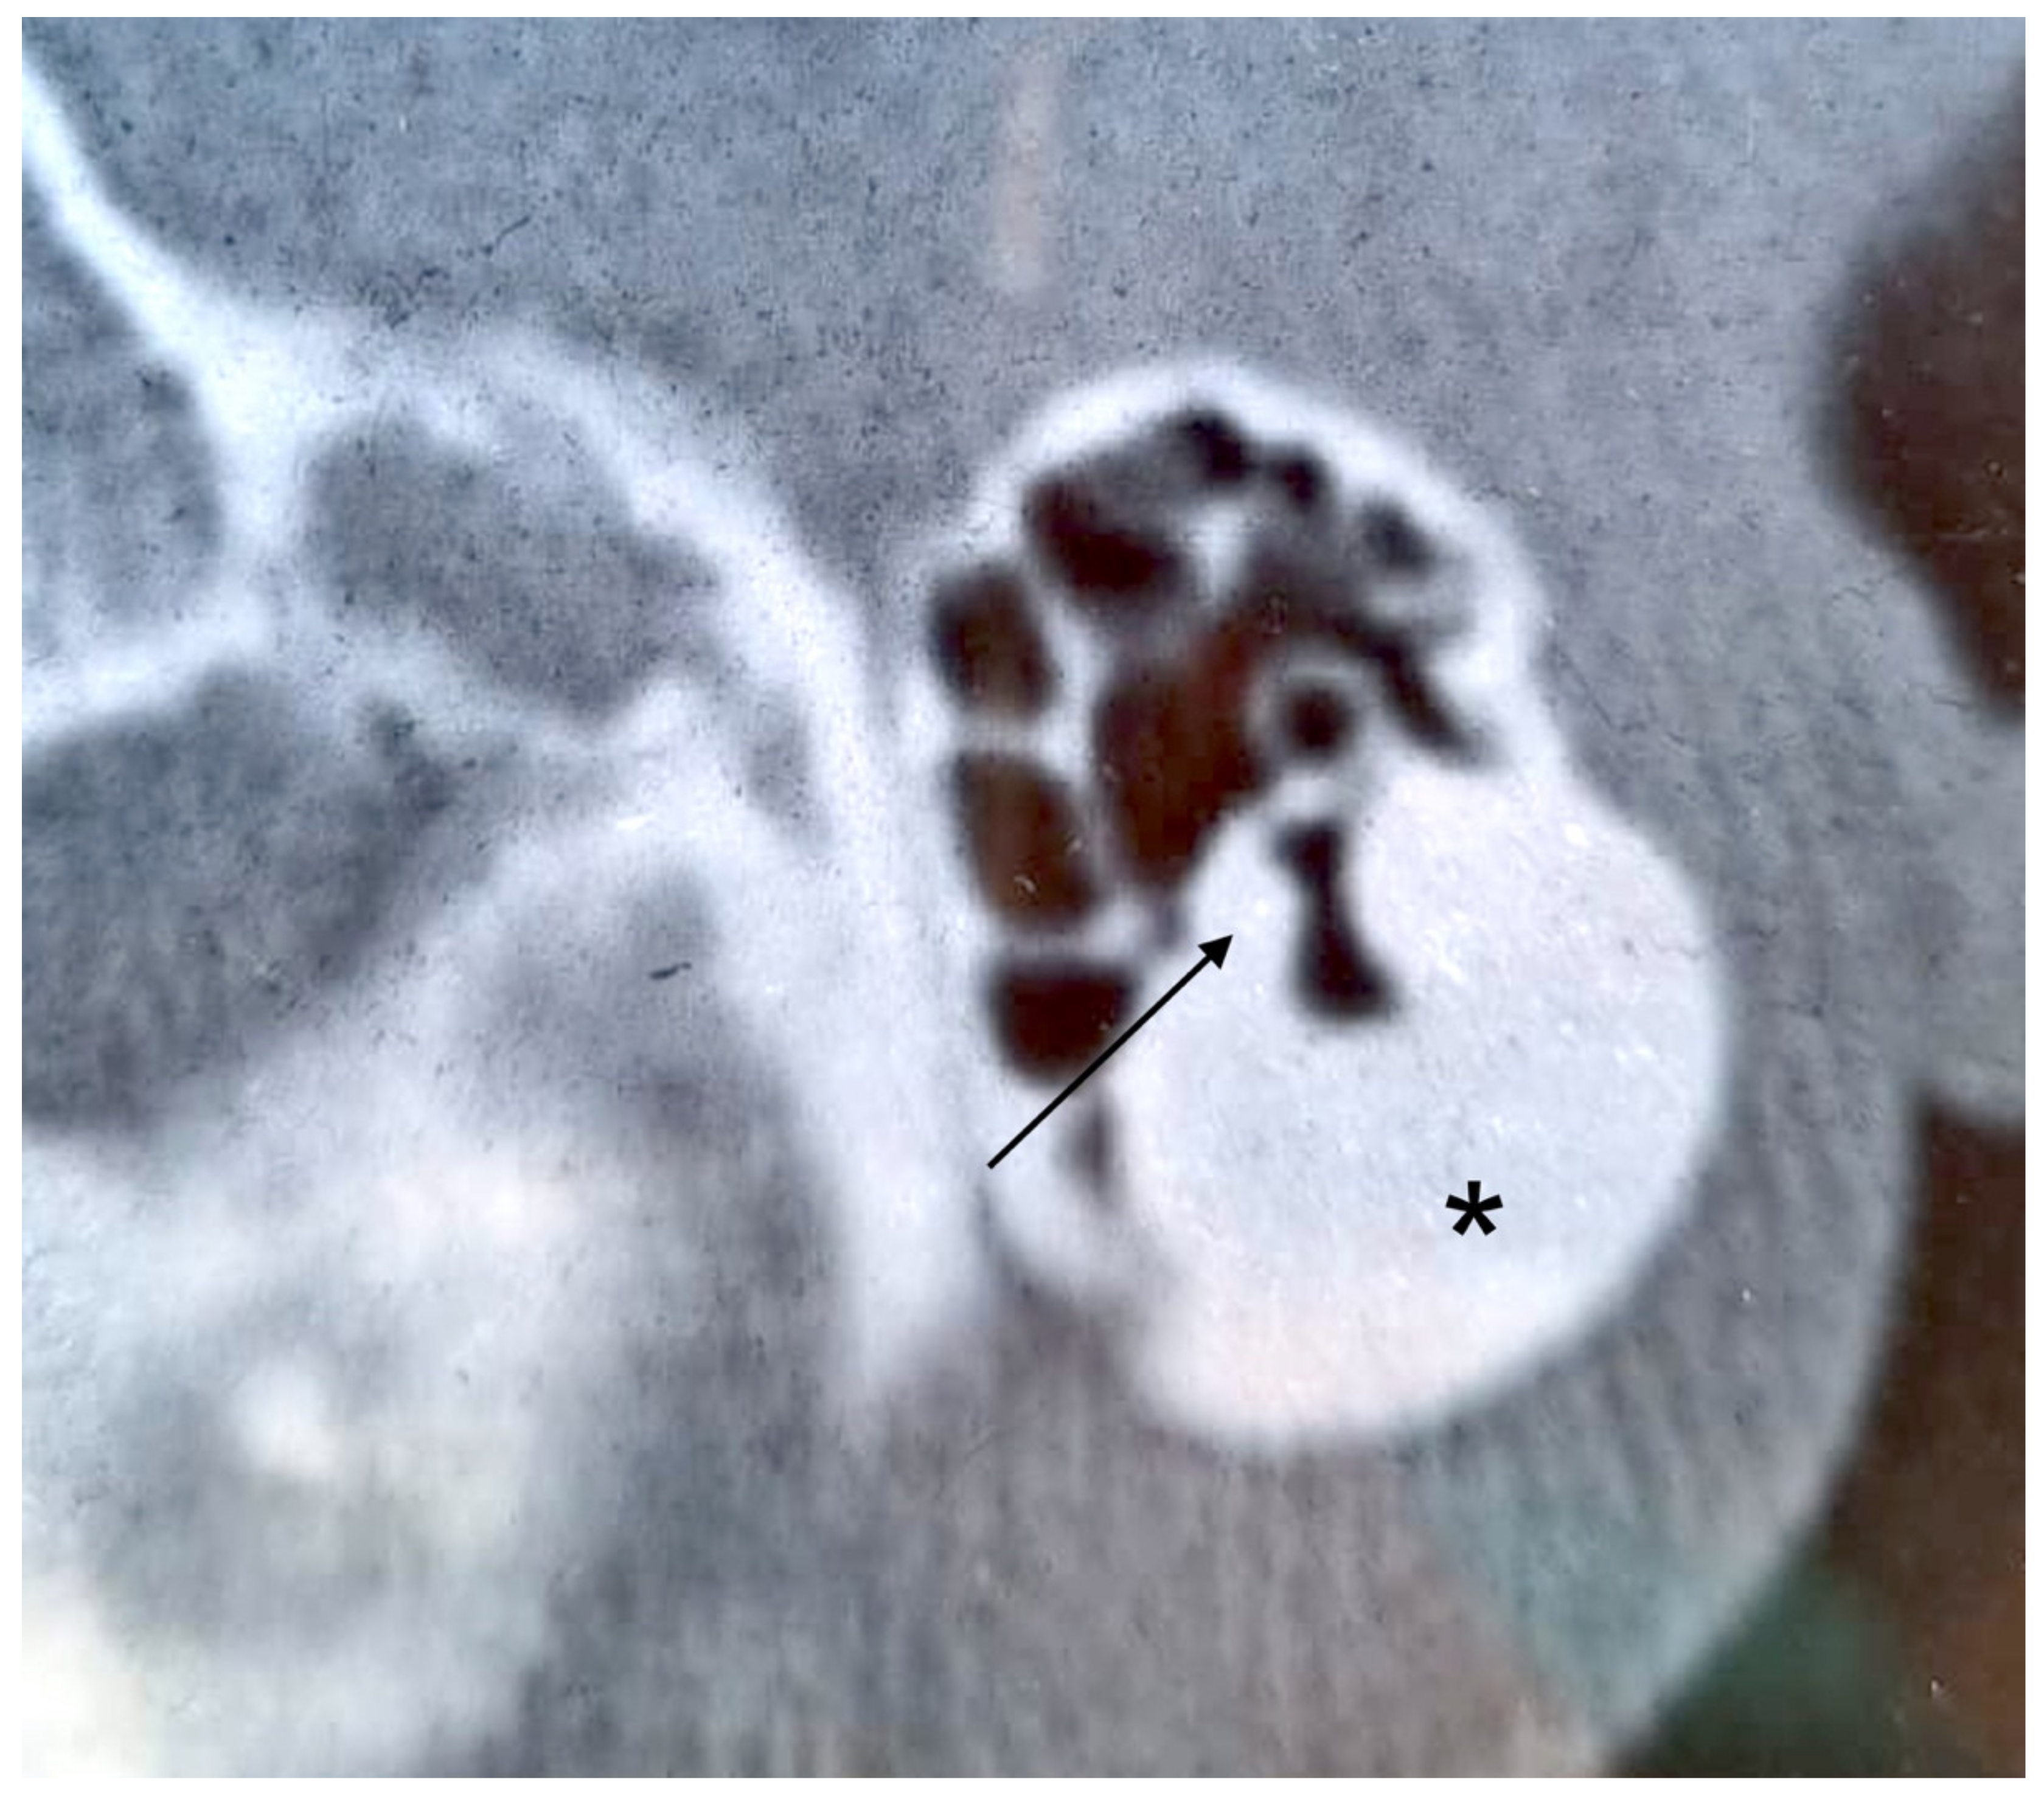

3.2. Case 2